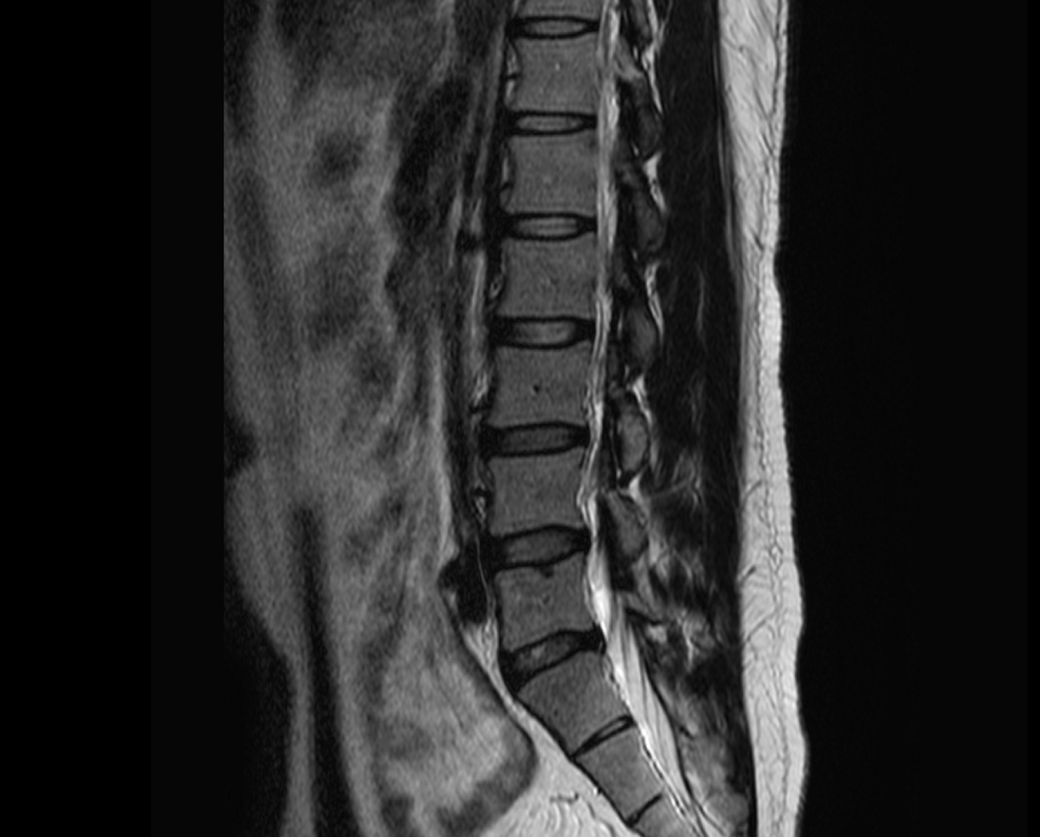

현재

• 4번 째 사진

1년 전 사진에 비해 허리디스크 상황이 악화된 것으로 생각됩니다. 다리저림은 이로 인한 증상으로 생각됩니다.

그러나, 말씀하신 내용과 검사결과만으로는 교통사고와의 연관성에 대해 단정지어 말하기는 어렵습니다. 증상이 점차 악화되어 발생한 것인지, 교통사고에 의해 갑자기 악화된 것인지에 대한 판단이 추가로 필요하겠습니다.